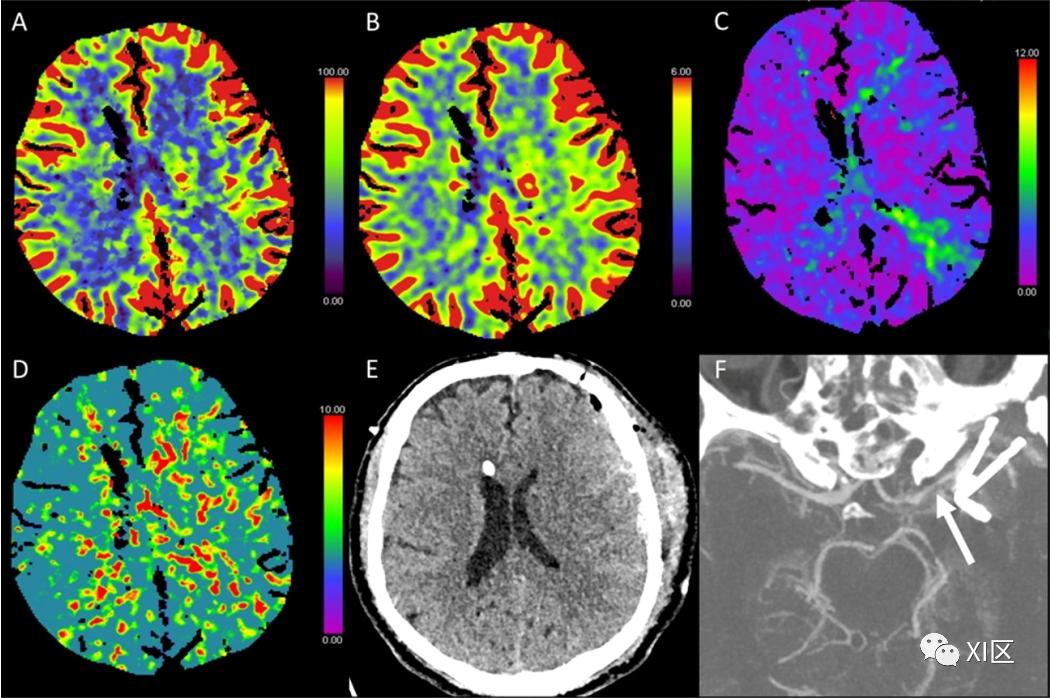

图1、图2、图3和图4给出了急性幕上卒中的例子。图5是一个恶性右侧MCA梗死的随访检查。

图3 脑部CTP生成的彩色编码图:(A)脑血流量(CBF)[mL/100 g/min],(B)脑血容量(CBV)[mL/100 g],(C)Tmax [s],以及(D)平均通过时间(MTT)[s]。(E)NECT和(F)动脉CT血管成像(CTA)最大密度投影(MIP)图像。该患者在经导管主动脉瓣植入术(TAVI)后出现异物感并昏迷。在NECT图像上,没有发现脑实质的缺血性改变。CTP发现CBF强烈降低,CBV正常,导致Tmax和MTT强烈延长,这与急性缺血事件相一致,表明有一个大的半影,没有环形的缺血核心。CTA显示基底动脉顶端有血栓性闭塞。